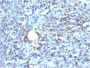

This antibody recognizes a glycoprotein of 110 kDa, which is identified as CD68. It is important for identifying macrophages in tissue sections. It stains macrophages in a wide variety of human tissues, including Kupffer cells and macrophages in the red pulp of the spleen, in lamina propria of the gut, in lung alveoli, and in bone marrow. It reacts with myeloid precursors and peripheral blood granulocytes. It also reacts with plasmacytoid T cells, which are supposed to be of monocyte/macrophage origin. It shows strong granular cytoplasmic staining of chronic and acute myeloid leukemia and also reacts with rare cases of true histiocytic neoplasia. Lymphomas are negative or show few granules. Primary antibodies are available purified, or with a selection of fluorescent CF® Dyes and other labels. CF® Dyes offer exceptional brightness and photostability. Note: Conjugates of blue fluorescent dyes like CF®405S and CF®405M are not recommended for detecting low abundance targets, because blue dyes have lower fluorescence and can give higher non-specific background than other dye colors.

Positive Control

U87MG, Tonsil, Lymph Node or Spleen.

IF (verified), IHC, FFPE (verified), WB (verified)

IF (verified)|IHC (FFPE) (verified)|WB (verified)